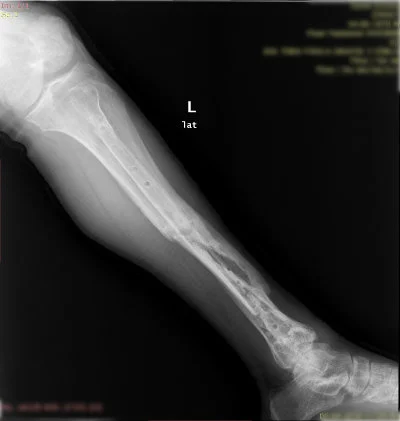

Görüntüleri büyütmek için resmin üstüne tıklayınız.